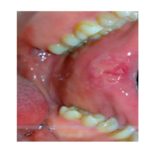

Cheratosi frizionale e morsicatio buccarum Premium

Differenti tipi di traumi possono essere alla base di queste due lesioni delle mucose orali e alcune categorie di pazienti sono più frequentemente coinvolte. Una panoramica degli aspetti epidemiologici e clinici per essere d’aiuto nell’intercettazione di tali condizioni.